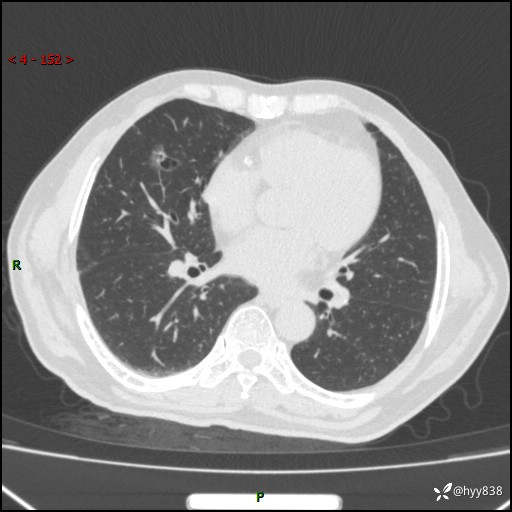

胸部CT复查(2024.7)